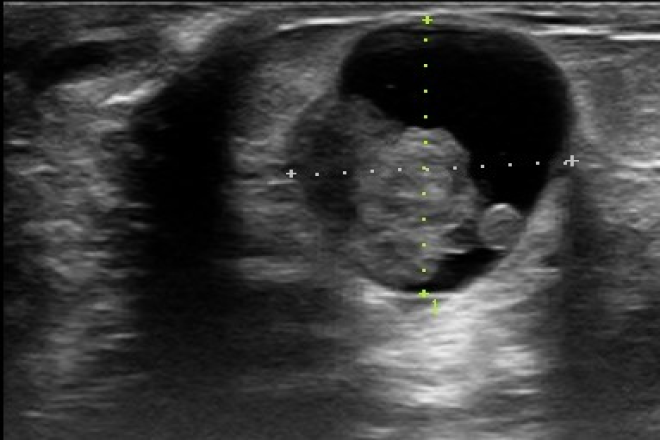

GALACTOCELE

Lesión mamaria poco frecuente, un quiste mamario es ocupado y rellenado por leche en la etapa de la lactancia. Clínicamente es un nódulo blando, indoloro, unilateral, de aprox 1-5cm que aparece semanas o meses después de iniciada la lactancia y con lactancia activa al momento del

diagnóstico, al suspender la lactancia puede persistir organizándose formando un nódulo caseificado bien delimitado. Al ultrasonido es de pared delgada y ecogénica, de ecos internos variables, asociado a un nivel graso-líquido en ocasiones. El tratamiento es punción evacuadora y escisión quirúrgica en caso de recurrencia.